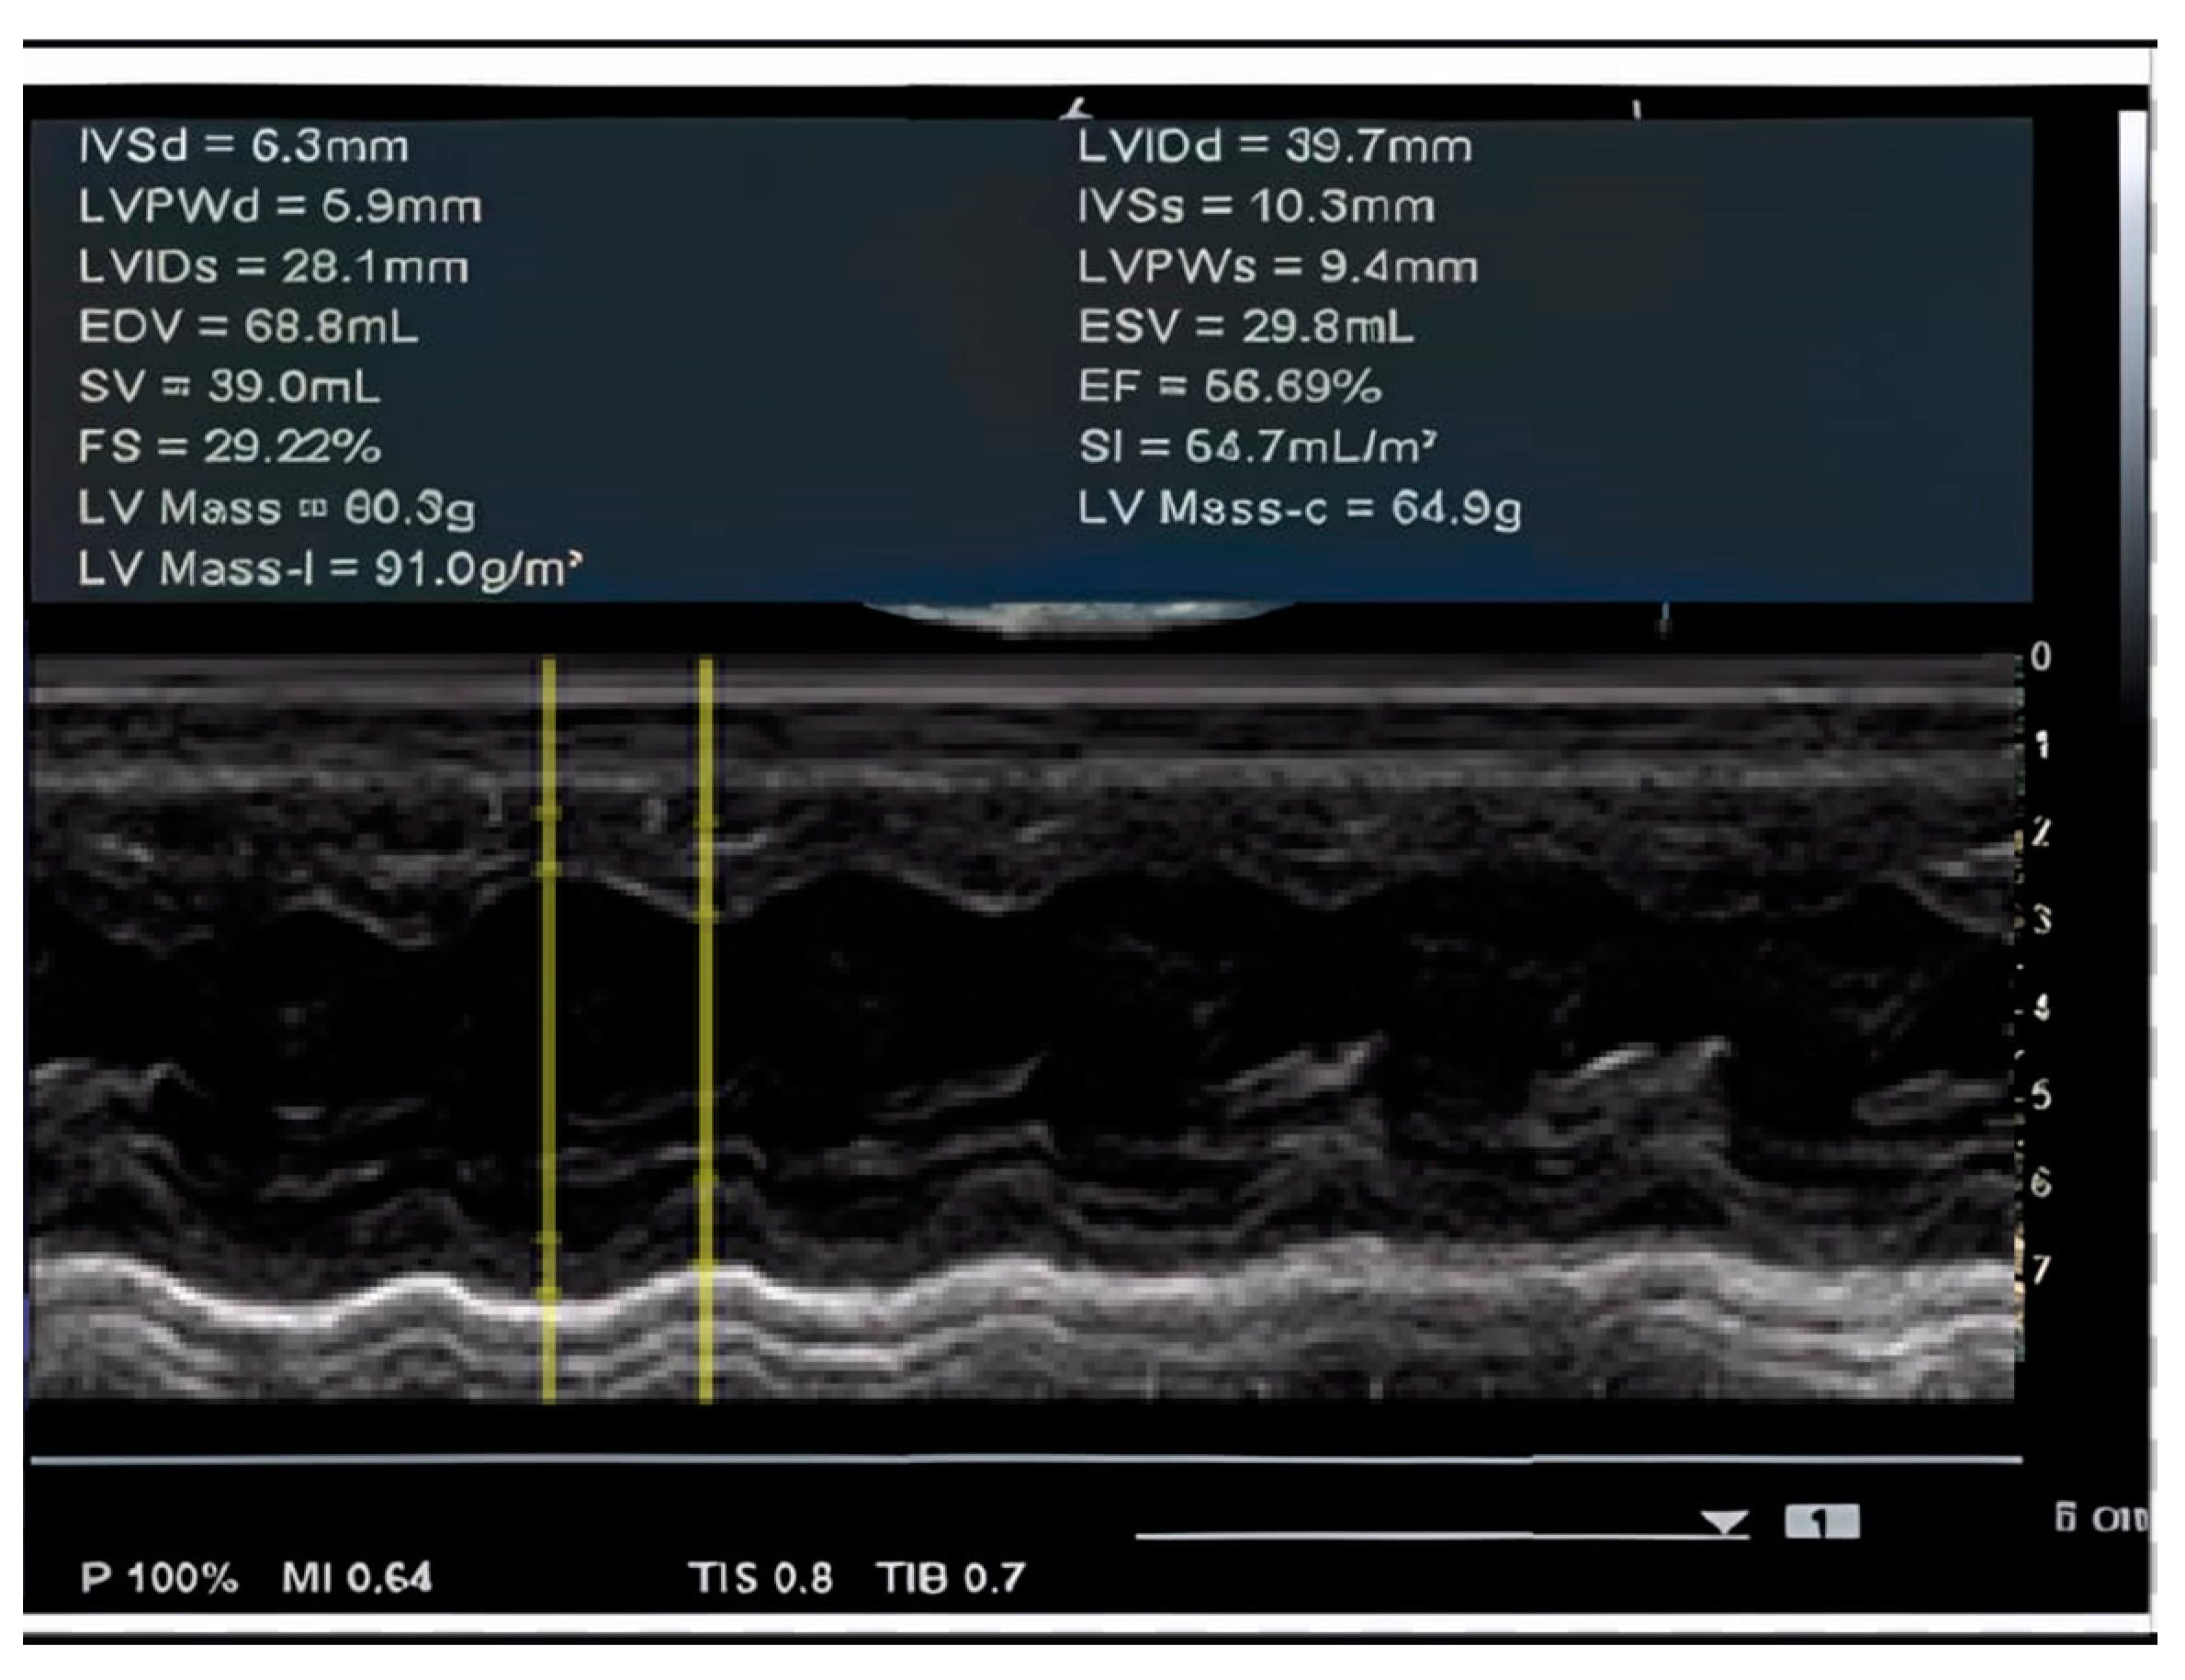

| 3 y 8 m | Cardiac dimensions: 17 mm at the ascending aorta, 30 mm at both LV and RV. Doppler flow velocities of 0.90 m/s Ao and 0.90 m/s at the PV. Mitral and aortic valves appear normal with normal motility. EF = 56.69%. Dilative cardiomegaly in an incipient form in the context of DMD. EKG: Sinus tachycardia with HR = 100 bpm, QRS axis at 0 degrees, juvenile ST-T pattern. |

| 6 y 3 m | Left ventricle dilated with normal systolic–diastolic function. |

| 8 y 1 m | Longitudinal dysfunction of the LV and RV. EKG: Sinus tachycardia with HR = 100 bpm, QRS axis at 0 degrees, juvenile ST-T pattern. |

| 9 y | LV slightly globular with normal global systolic function. Normal diastolic function. No valvulopathies. No pulmonary hypertension. BP = 100/60 mmHg; HR = 75 bpm; no murmurs. EKG: Sinus rhythm with HR = 90 bpm, QRS axis = +45 degrees, PR interval = 0.12 s, juvenile ST-T pattern. |

| 10 y 5 m | LV globular. Longitudinal dysfunction of the LV. BP = 100/60 mmHg, HR = 90 bpm, grade I/VI systolic murmur heard at the left parasternal border. EKG: RBBB. |

| 11 y 4 m | LV globular with preserved ejection fraction. Longitudinal dysfunction of the LV. EKG: Sinus tachycardia HR = 110 bpm, QRS axis +60 degrees, PR interval: 0.18 s, RBBB with secondary ST-T changes. |